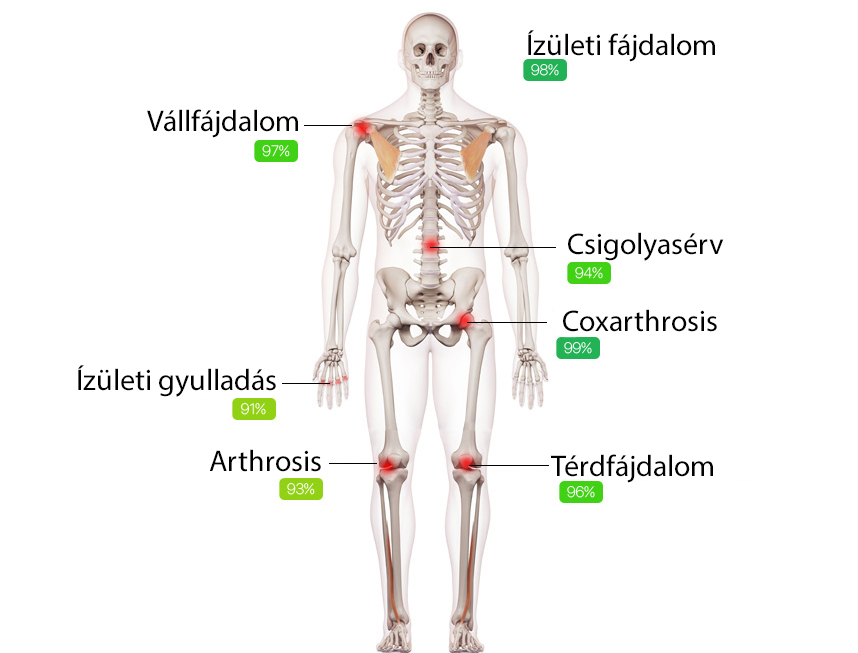

Miért van szüksége a HondroLife-ra?

A készítmény kiegyensúlyozott formulájának köszönhetően a HondroLife védelmet nyújt a gyulladásokkal és hatékony szövetnövekedéssel szemben. Ezenkívül összetett módon hat a következő hatással:

A HondroLife megoldja a legtöbb

ízületi

problémát

82%-os hatékonyság

hogy segít

megoldani

az ízületi és a mozgásszervi próblémákat

.